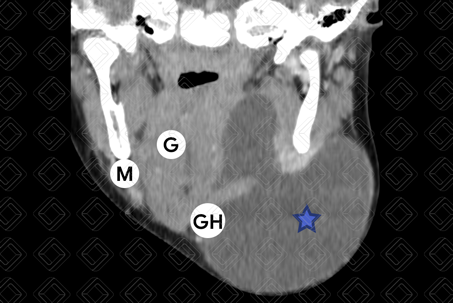

Texto alternativo para a imagem Figura 4. Créditos: Dra. Elazir Mota - Rio de Janeiro/RJ

Descrição das figuras 3, 4 e 5: Tomografia computadorizada do pescoço após administração do contraste venoso, evidenciando rânula mergulhante. Observe a formação cística (asteriscos) no espaço sublingual (seta vermelha) esquerdo, estendo para região submentoniana e submandibular deste lado devido à falha na musculatura milo-hioidea. Legenda: GH = gênio-hioideo; G = genioglosso; M = milo-hioideo; D = digástrico.